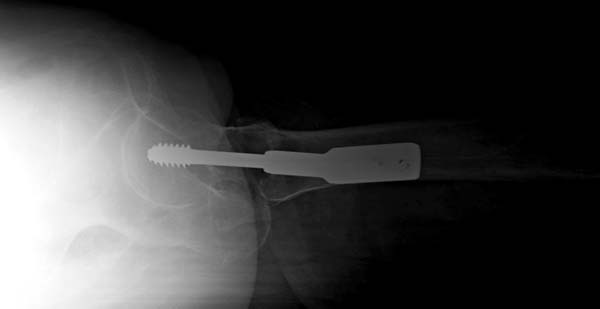

Вторую проекцию после остеосинтеза легко сделать тем же Арманом.

Поставить его как на фас, но согнуть ногу в тазобедренном и коленном суставах на 90 градусов и чуть отвести. Бедро не ротировать, т.е. голень

чтобы была параллельна оси туловища.

Сегодня сделал р-снимок, как было сказана,

но получилось не качественная, р-аппарат "Арман" старенький, недавно получили новый "Сименс" , скоро запустим!

То-что получилось отправляю, за качества извиняюсь!